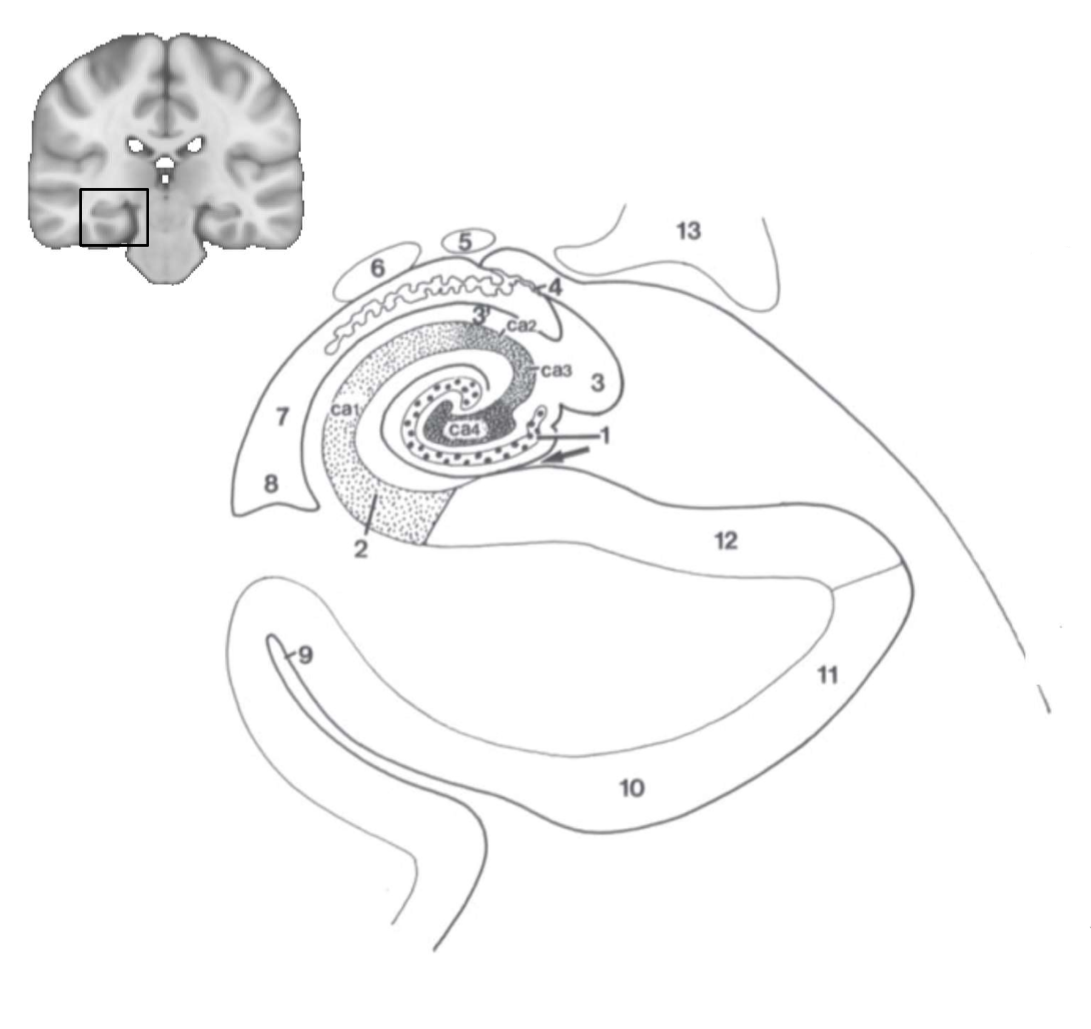

What structure is this?

hippocampus

What is 1?

hippocampus

What is 2?

rhinal sulcus

What is 3?

lateral ventricle

What is 4?

thalamus

What is 5?

entorhinal cortex

What is 6?

perirhinal cortex

What is 7?

parahippocampal cortex

What is 1?

gyrus dentatus

What is 2?

cornu ammonis

What is 3?

fimbria

What is 3’?

alveus

What is the arrow pointing to?

happicampal sulcus

What is ca1, ca2, ca3 and ca4?

fields of cornu ammonis

What is 4?

tela choroidea

What is 5?

stria terminalis

What is 6?

tail of caudate nucleus

What is 7?

temporal horn of lateral ventricle

What is 8?

collateral eminence

What is 9?

collateral sulcus

What is 10?

parahippocampal

What is 11?

entorhinal area

What is 12?

subiculum

What is 13?

lateral geniculate body